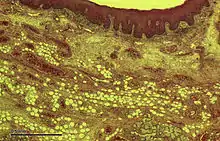

_Section.jpg.webp)

The upper surface of the tongue is covered in masticatory mucosa, a type of oral mucosa which is of keratinized stratified squamous epithelium. Embedded in this are numerous papillae, some of which house the taste buds and their taste receptors.[9] The lingual papillae consist of filiform, fungiform, vallate and foliate papillae,[5] and only the filiform papillae are not associated with any taste buds.

The tongue can divide itself in dorsal and ventral surface. The dorsal surface is a stratified squamous keratinized epithelium which is characterized by numerous mucosal projections called papillae.[10] The lingual papillae covers the dorsal side of the tongue towards the front of the terminal groove. The ventral surface is stratified squamous non-keratinized epithelium which is smooth.[11]